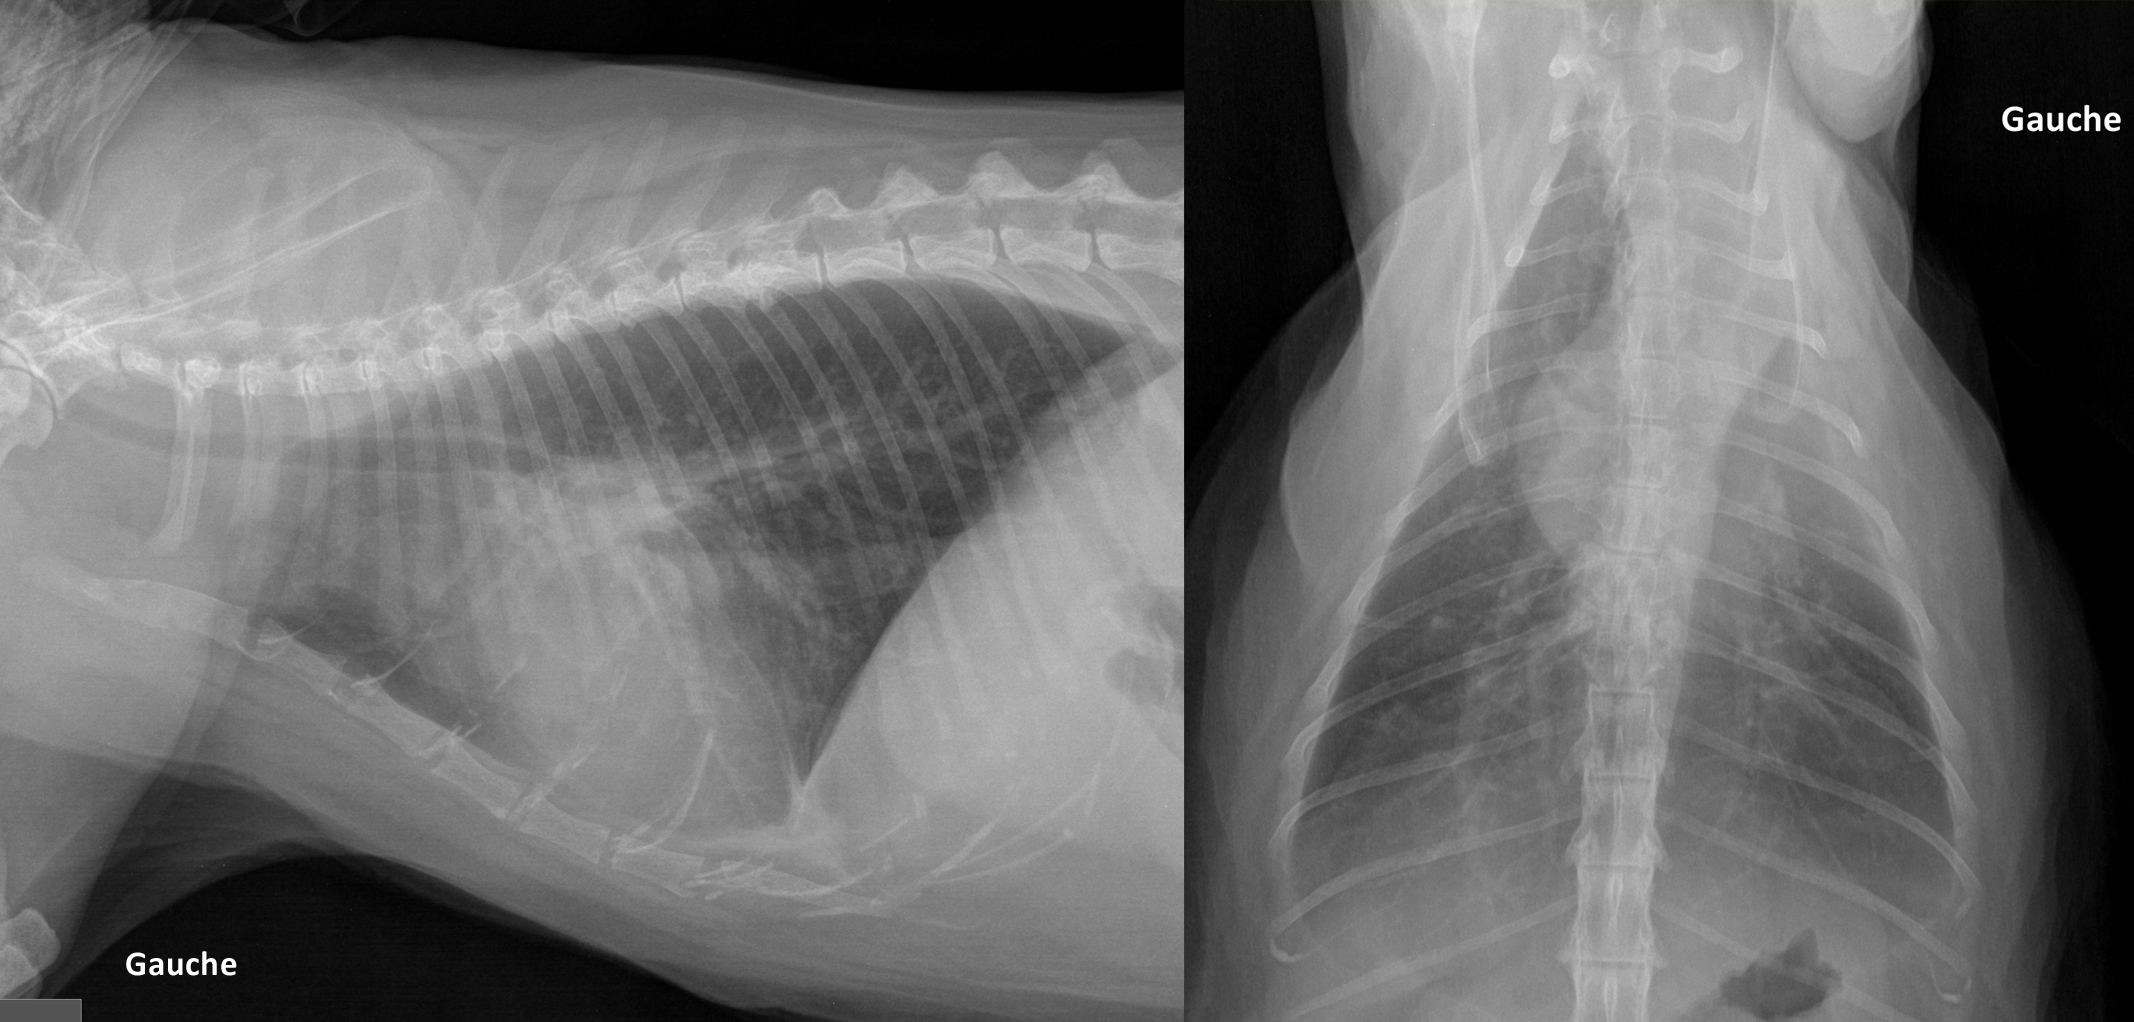

Signalement: chat domestique, femelle opérée de 12 ans

Histoire clinique: anorexie, perte de poids, vomissements